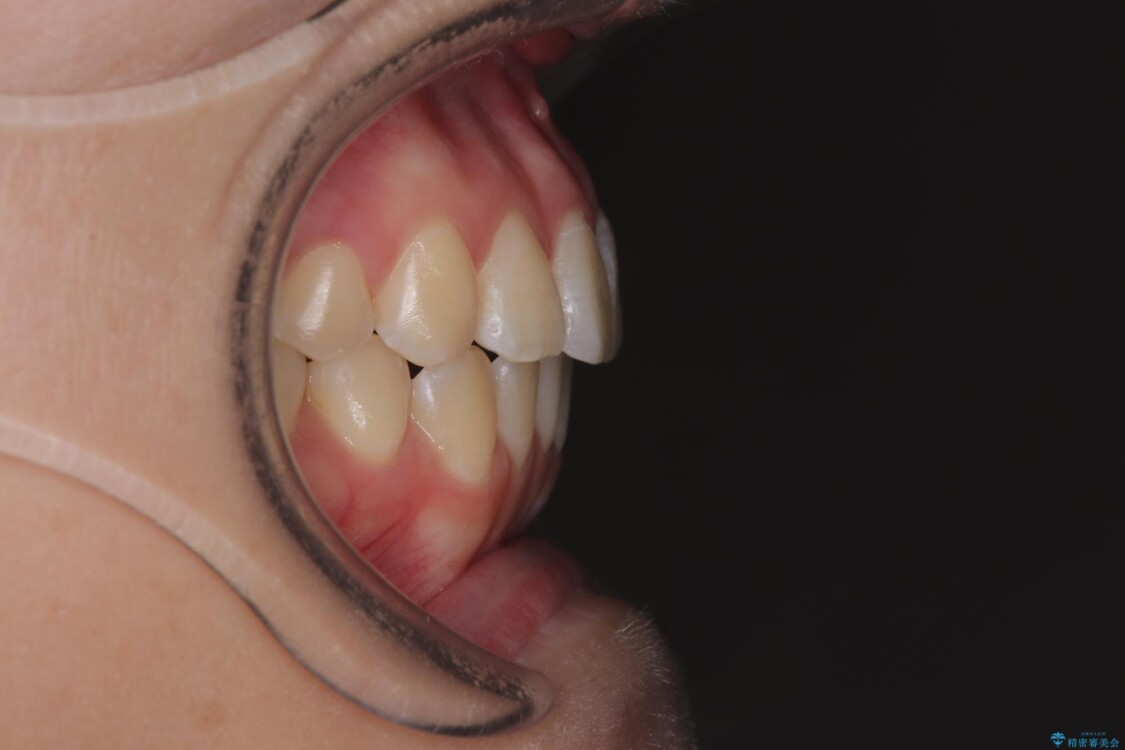

診察の結果、上下の前歯部に**叢生(そうせい/歯のガタガタ・重なり)**が認められました。

特に上の前歯にはねじれや重なりがあり、審美的にも清掃性にも影響している状態でした。

治療前

• 前歯のねじれ・ガタガタを10か月で改善!20代女性の矯正治療|クリアブラケットでむし歯になりにくい歯並びへ改善 治療前画像